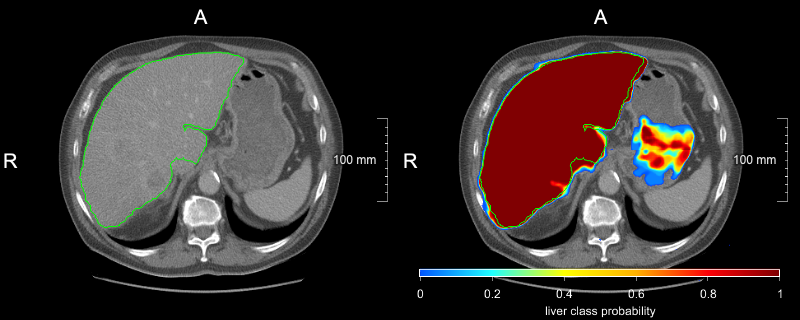

(a) Polycystic liver case where the USS strategy resulted in the best segmentation: UVS 0.83 Dice, 25.2% RVE, 8.0 mm MSD, 64 mm HD; RVS 0.53, 63.2%, 18.0 mm, 64 mm; USS 0.94, 5.2%, 3.2 mm, 59 mm; RSS 0.84, 21.7%, 8.7 mm, 65 mm; Data Pool 0.85, 24%, 8.3 mm, 64 mm.

Refer to caption

(b) Case where UVS outperformed all models: UVS 0.96 Dice, 0.4% RVE, 1.1 mm MSD, 17 mm HD; RVS 0.96, 3.1%, 1.4 mm, 21 mm; USS 0.94, 5.6%, 1.5 mm, 24 mm; RSS 0.95, 2.5%, 1.4 mm, 22 mm; Data Pool 0.93, 9.1%, 2.1 mm, 32 mm.

(c) Case where both random strategies resulted in overestimation in the caudal liver region: UVS 0.91 Dice, 6.1% RVE, 2.4 mm MSD, 23 mm HD; RVS 0.93, 3.4%, 2.1 mm, 25 mm; USS 0.95, 1.0%, 1.5 mm, 17 mm; RSS 0.77, 41.0%, 23.3 mm, 141 mm; Data Pool 0.94, 0.2%, 1.7 mm, 21 mm.

(d) Case for which all strategies except RVS achieved very good segmentation performance: UVS 0.97 Dice, 0.1% RVE, 0.9 mm MSD, 18 mm HD; RVS 0.91, 11.8%, 2.9 mm, 36 mm; USS 0.96, 1.8%, 1.0 mm, 20 mm; RSS 0.97, 1.6%, 0.9 mm, 20 mm; Data Pool 0.97, 0.0%, 0.8 mm, 20 mm.

Figure 3: Representative examples presenting segmentation output of the converged models and the model trained on the whole data pool.

In our work, we proposed the uncertainty slice sampling (USS) strategy in the context of pool-based active learning. Our strategy selects 2D image slices from a pool of 3D volumes using aggregated voxel-wise predictive entropy as the uncertainty measure. We evaluated the proposed strategy on a CT liver segmentation task and compared it with random slice sampling (RSS), uncertainty volume sampling (UVS), and random volume sampling (RVS) strategies. The model trained using the USS data (4% of available data) achieved significantly better results than the remaining strategies. Although after five active learning iterations the USS model was inferior in performance on average to the model trained on all available data, it provided more robust segmentation as measured by 5th DICE and 95th MSD metrics. We hypothesize that this can be attributed to differences in the training set composition. The training set resulting from the USS contains a bigger proportion of difficult/rare cases compared to the whole data-pool training set, which effectively causes that the model sees them more frequently during the training process. Fig. 3 shows exemplary outputs from the investigated models including two hard cases from the test set: a polycystic (Fig. 3(a)) and a resected (Fig. 3(b)) liver. We think that the robustness of the whole data pool model could be increased by employing a hard example mining during training to dynamically adjust the sampling rate of difficult examples[26, 27]. Selecting only uncertain cases in the course of active learning can overload the model with difficult examples causing a performance drop. This can be observed for the USS strategy after the first iteration (see Fig. 1, where the model performs substantially worse than its random counterpart (RSS).